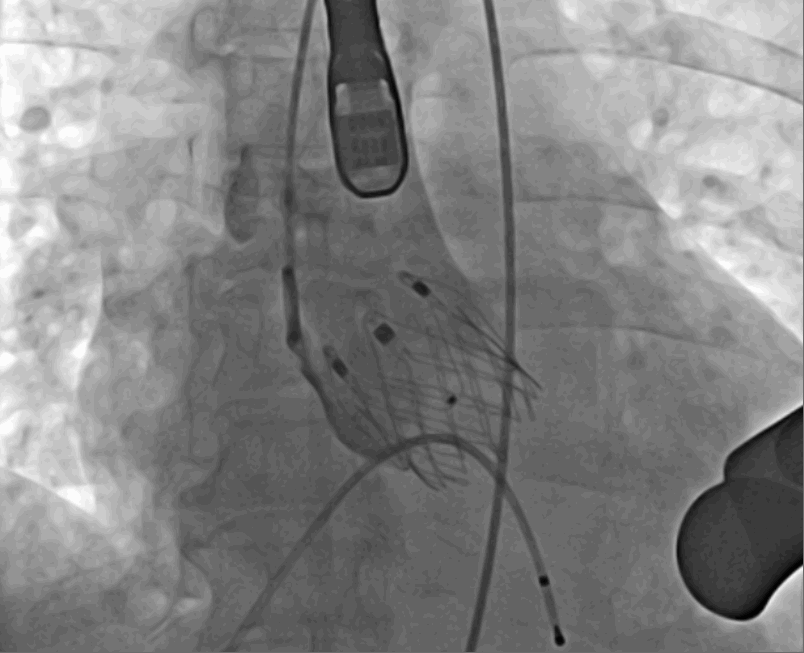

術(shù)中釋放定位鍵后DSA影像圖

術(shù)中瓣膜釋放過(guò)程